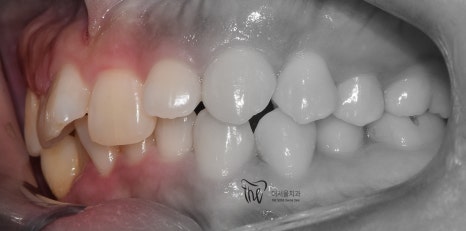

『23개월 소요, 최종 결과』

앞니의 기울기 변화에 따라서, 입술의 긴장감 또한

변화가 일어났습니다.

심미선을 기준으로, 입술의 위치가 그렇게

많이 변화가 된 것은 아니나 어찌되었건간에

심미선 안쪽에 입술이 위치 되는 것을 보실 수

있네요.

그러면서, 교정치료가 다 끝나가는 시점에서

임플란트를 심어서 맞물리는 대합치와의

기능 재건도 같이 진행했습니다.

정면에서 봤을 때, 앞니들 사이에 블랙트라이앵글이

조금씩 발생 된 부분은 살짝 아쉽긴 합니다.

그러나, 이는 과거 총생이 너무 심했기 때문에

어쩔 수 없이 발생이 될 수 밖에 없는 상황이였으며

이것을 제외하곤, 환자께서 얻으신 것이 많습니다.

그러나, 최종 결과를 보면 과개교합이 많이

개선이 된 것도 같이 보실 수 있네요.^^